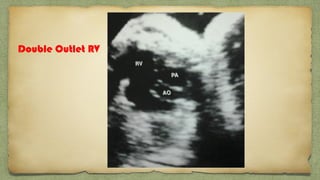

Double Outlet RV

TGA